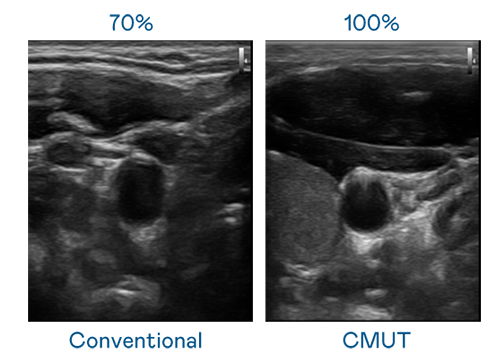

CMUT 技术是一种用电容式微机电元件来产生超音波讯号的技术。与传统 PZT 压电式技术相比,CMUT 频宽增加 30%,更宽频的超音波讯号让影像解析度大幅提升,是实现高影像品质医疗超音波扫描、促进精准医疗发展的关键技术。

超音波影像的解析度高低,首先取决于探头能发出的讯号频宽。完美真人WM CMUT 可提供高清晰的超音波讯号,提供高频宽、高灵敏度、影像纹理细节更高的超音波影像,协助医护人员缩短影像判读时间及利用精准的医疗影像进行诊断。